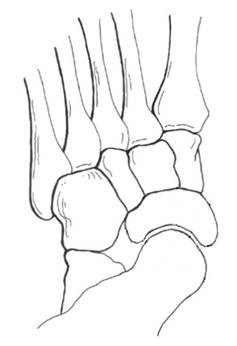

| 影像学检查 X线是诊断扁平足的常用方法,其中负重正侧位X线是最为常用的诊断方法。通过测量多个角度来评价内侧纵弓的降低,前足的外展以及跟腱的挛缩程度。并根据这些指标指导临床治疗方式的选择。扁平足的X线测量指标主要有:1.负重侧位X线片:距骨第1跖骨角,跟骨倾斜角等。2.负重正位X线片:距舟覆盖角,距骨第2跖骨角等。其中侧位距骨第1跖骨角被认为是X线上评价扁平足最有意义的指标。除此之外还可应用Saltzman位X线及后足长轴位X线评价后足内外翻程度。 常用影像学检查: | |

| 相关X线测量 | |

| – 正位: 距舟覆盖角 距骨第2跖骨角 – 侧位: 骨第1跖骨角(Meary) 跟骨倾斜角(Pitch)